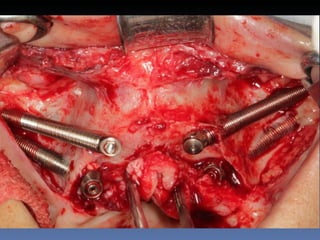

BOX 2

Sebastião Moreira Souza

Idade – 49 anos

Sexo – Masculino

Raça – Caucasiana

ASA – II

Data- 23-04-2012

Diagnóstico: Desdentado total maxila

Plano de tratamento:          Reabilitação com 6 blocos

“onlay” e “sinus-llift” bilateral, provenientes de Úmero

fresco-congelado (FFB); reabertura para instalação

de 6 implantes dentários endo-ósseos e reabilitação

protética fixa.

21-09-2011

23-04-2012

Zona 2.3

3,5 mm

Pré reabilitação

Reabilitação Aloenxerto

Instalação Implantes